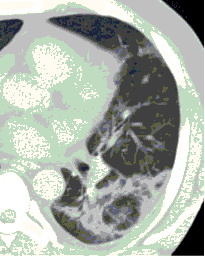

КТ имеет высокую чувствительность в выявлении изменений в легких, характерных для COVID-19. Применение КТ целесообразно для первичной оценки состояния ОГК у пациентов с тяжелыми прогрессирующими формами заболевания, а также для дифференциальной диагностики выявленных изменений и оценки динамики процесса. КТ позволяет выявить характерные изменения в легких у пациентов с COVID-19 еще до появления положительных лабораторных тестов на инфекцию с помощью МАНК. В то же время, КТ выявляет изменения легких у значительного числа пациентов с бессимптомной и легкой формами заболевания, которым не требуется госпитализация. Результаты КТ в этих случаях не влияют на тактику лечения и прогноз заболевания при наличии лабораторного подтверждения COVID-19. Поэтому массовое применение КТ для скрининга асимптомных и легких форм болезни не рекомендуется. При первичном обращении пациента с подозрением на COVID-19 рекомендуется назначать КТ только при наличии клинических и инструментальных признаков дыхательной недостаточности (SpO2 < 95%, ЧДД > 22).

3. Применение лучевых методов у пациентов с симптомами ОРВИ легкой степени тяжести и стабильном состоянии пациента, возможно только по конкретным клиническим показаниям, в том числе при наличии факторов риска, при условии достаточных технических и организационных возможностей. Методом выбора в этом случае является КТ легких по стандартному протоколу без внутривенного контрастирования или РГ при ограниченной доступности КТ. Использование УЗИ в этих случаях нецелесообразно. Применение КТ исследования в сроки ранее 3 - 5 дней с момента появления симптомов заболевания, а также при отсутствии клинических проявлений поражения бронхолегочной системы является нецелесообразным. Выполнение КТ целесообразно при наличии клинических и инструментальных признаков дыхательной недостаточности (SpO2 < 95%, ЧДД > 22), либо при дифференциальной диагностике с другим заболеванием.